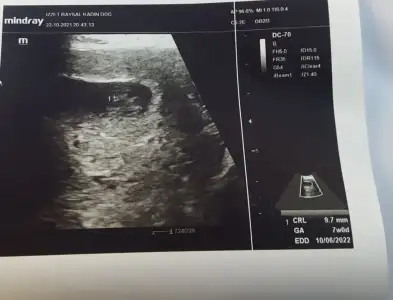

Kesede ilk gördüğünüz usg görüntüsü varsa 6.haftalardan falan bi gönder bakalım. 😉

Oyy maşallah çok şükür canım ne güzel gözüküyor demi kıpır kıpır oynaması 🥰bende çok şaşırmıştım 9 haftada görünce